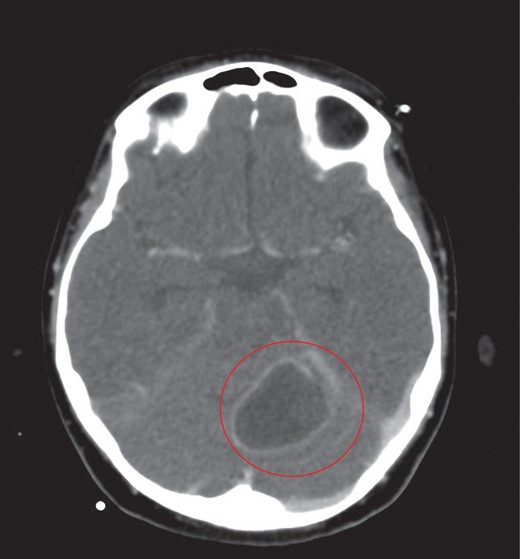

The cerebellar brain abscess was drained surgically, with pus sent for microscopy and culture. This returned gram negative coliform organisms and pus cells. The antibiotic therapy was modified to account for the new microbial sensitivities. The appearances of both the brain and chest improved over the next 10 days with complete resolution of the intracerebral abscesses and thrombosis (Fig. 8). There was a slower resolution of the chest. The patient was discharged from our institution after 16 weeks.

Eventual complete resolution of the brain abscesses and sinus/ IJV thrombosis.